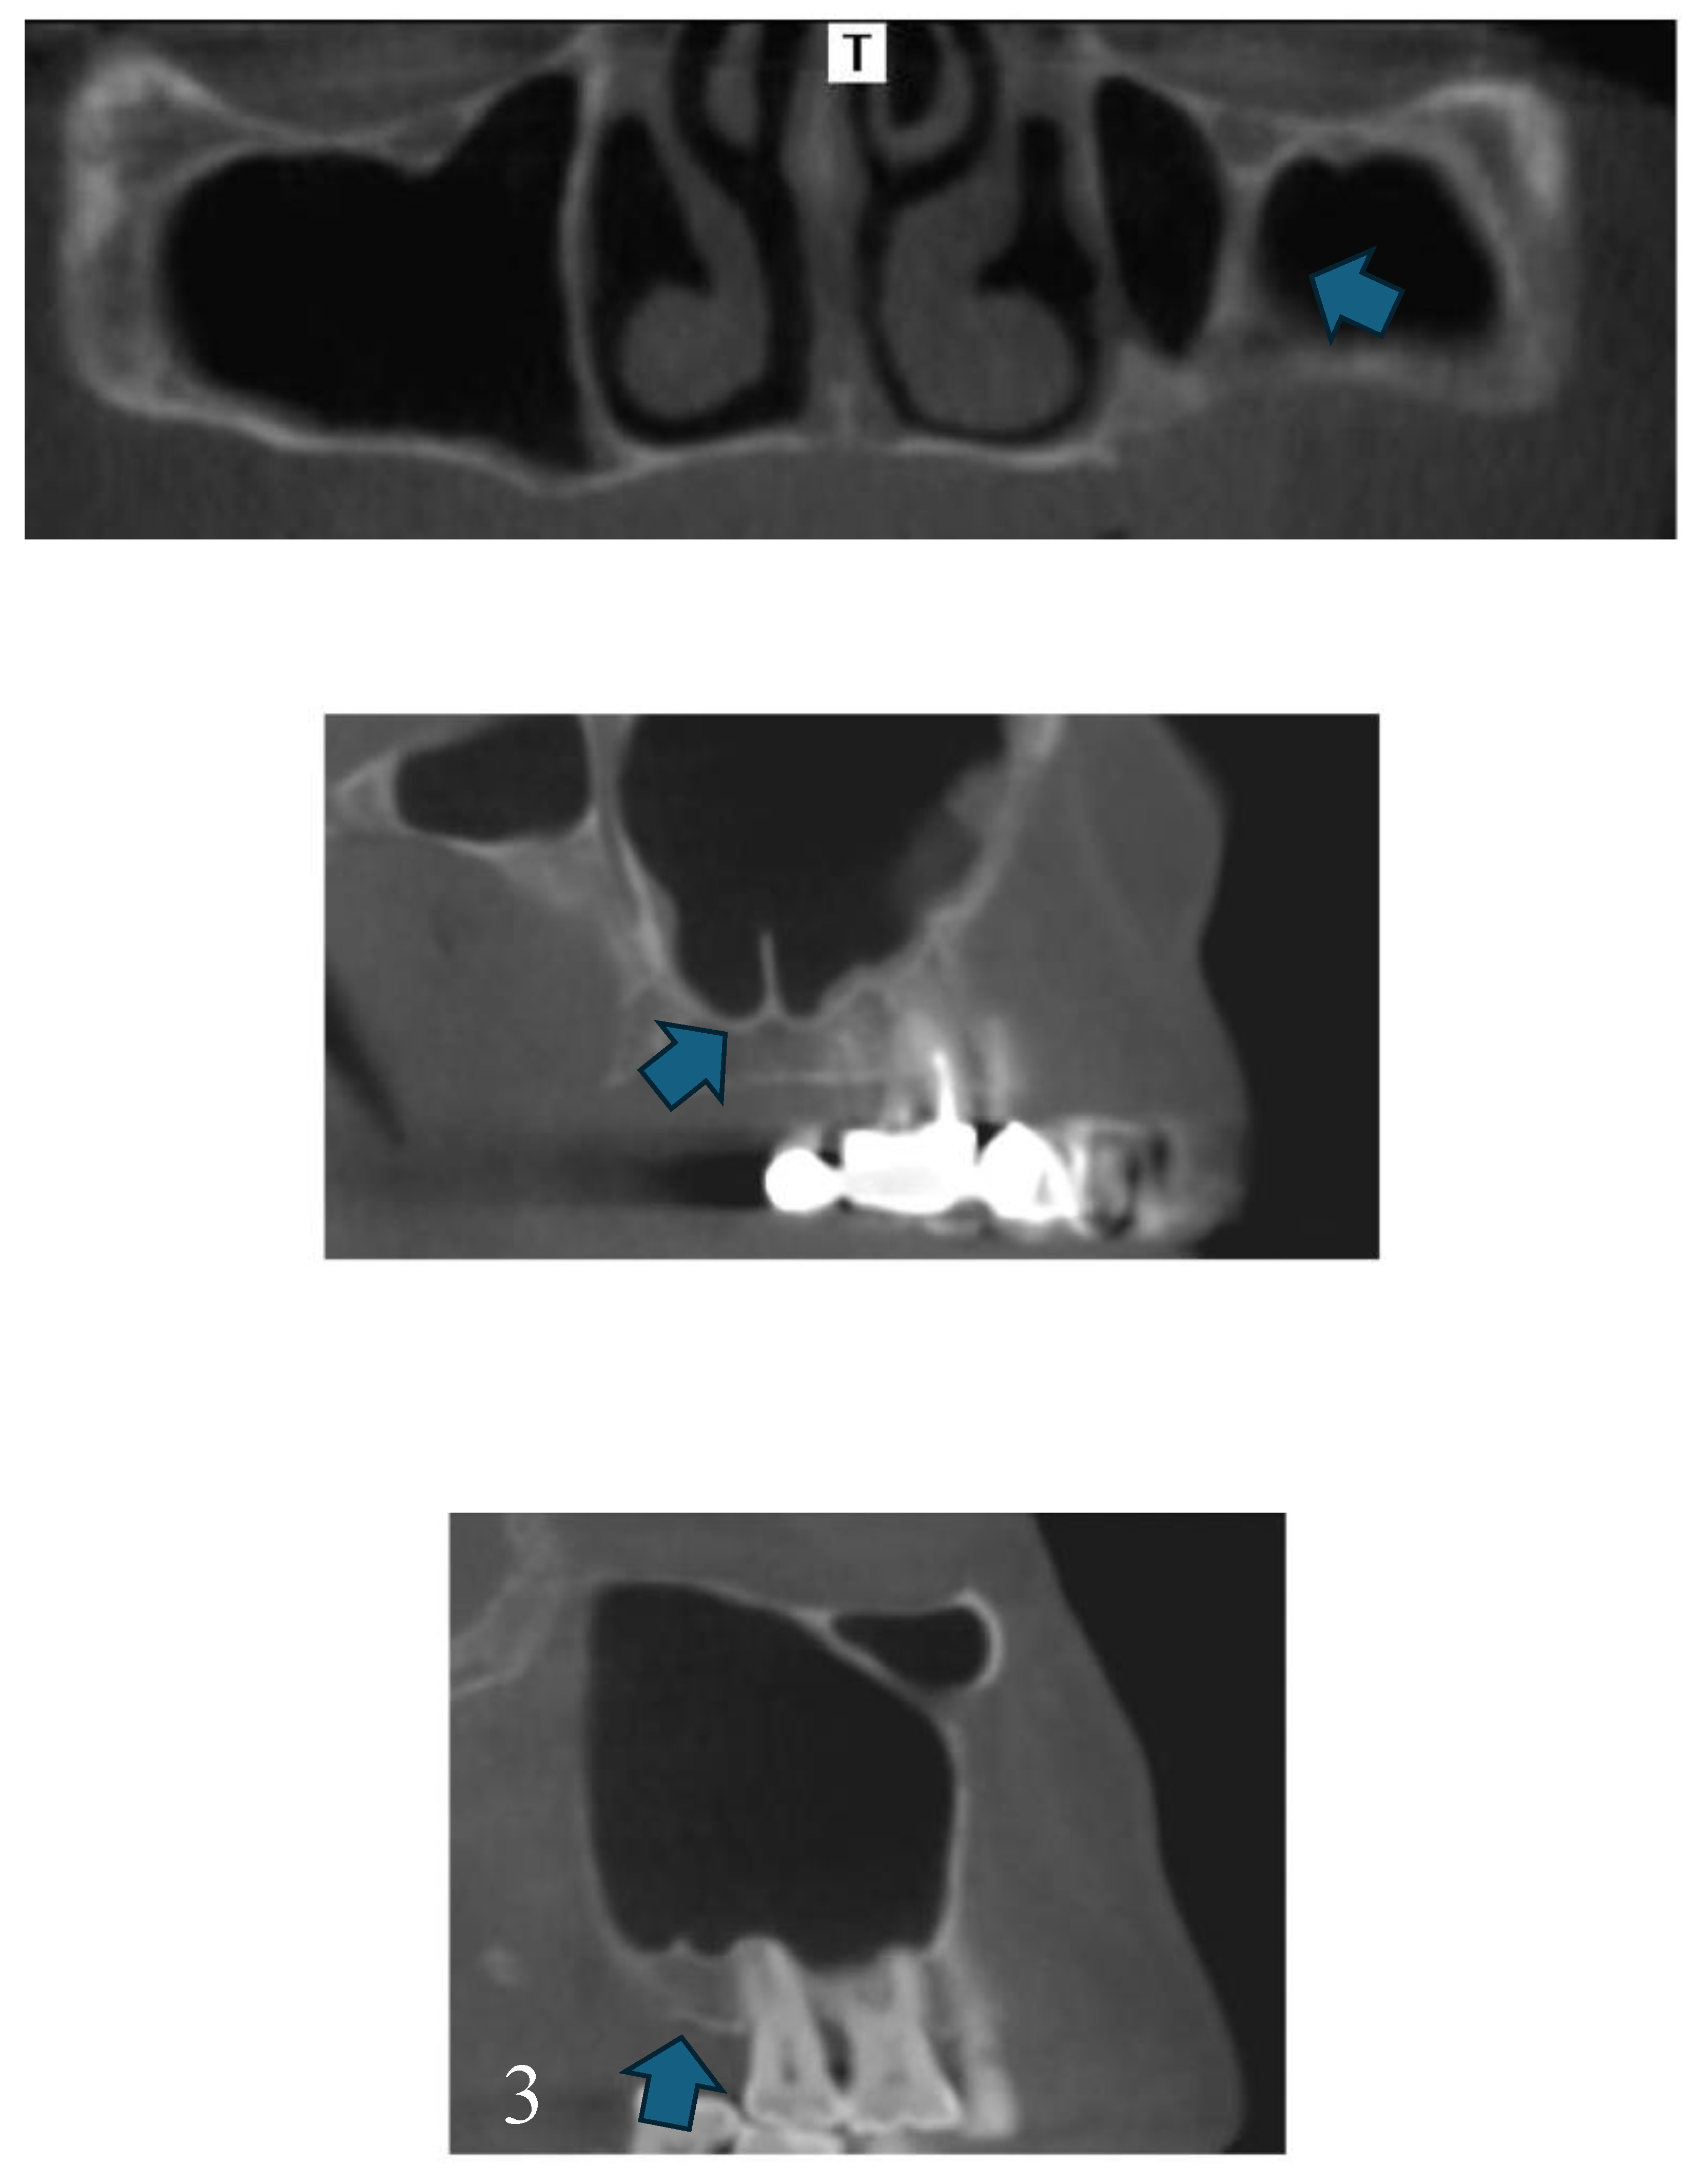

Maxillary Sinus

Septa

Posterior superior alveolar artery